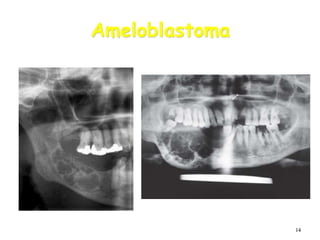

Ameloblastoma

• Benign but locally invasive neoplasm.

• Arises from epithelial remnants of dental

lamina or dental organ.

• Cells do not differentiate enough to form

enamel.

• Extreme expansion of bone,

• Resorption of adjoining roots.

• May cause perforation of cortical bone.

• Average age at discovery: 35-40 years.

• Most often a well-corticated multilocular

radiolucency.

• “Honey-comb”, “soap-bubble” or “tennis-racket”

appearance.

• May be a well-corticated unilocular lesion

Large multilocular soap bubble appearance.

Typically located in the molar region, angle of the

mandible and ascending ramus

Thin not penetrated cortical plate.

Impacted or neighboring teeth are displaced with

roots often resorped.

• Large ameloblastoma in the right ascending

ramus of the mandible